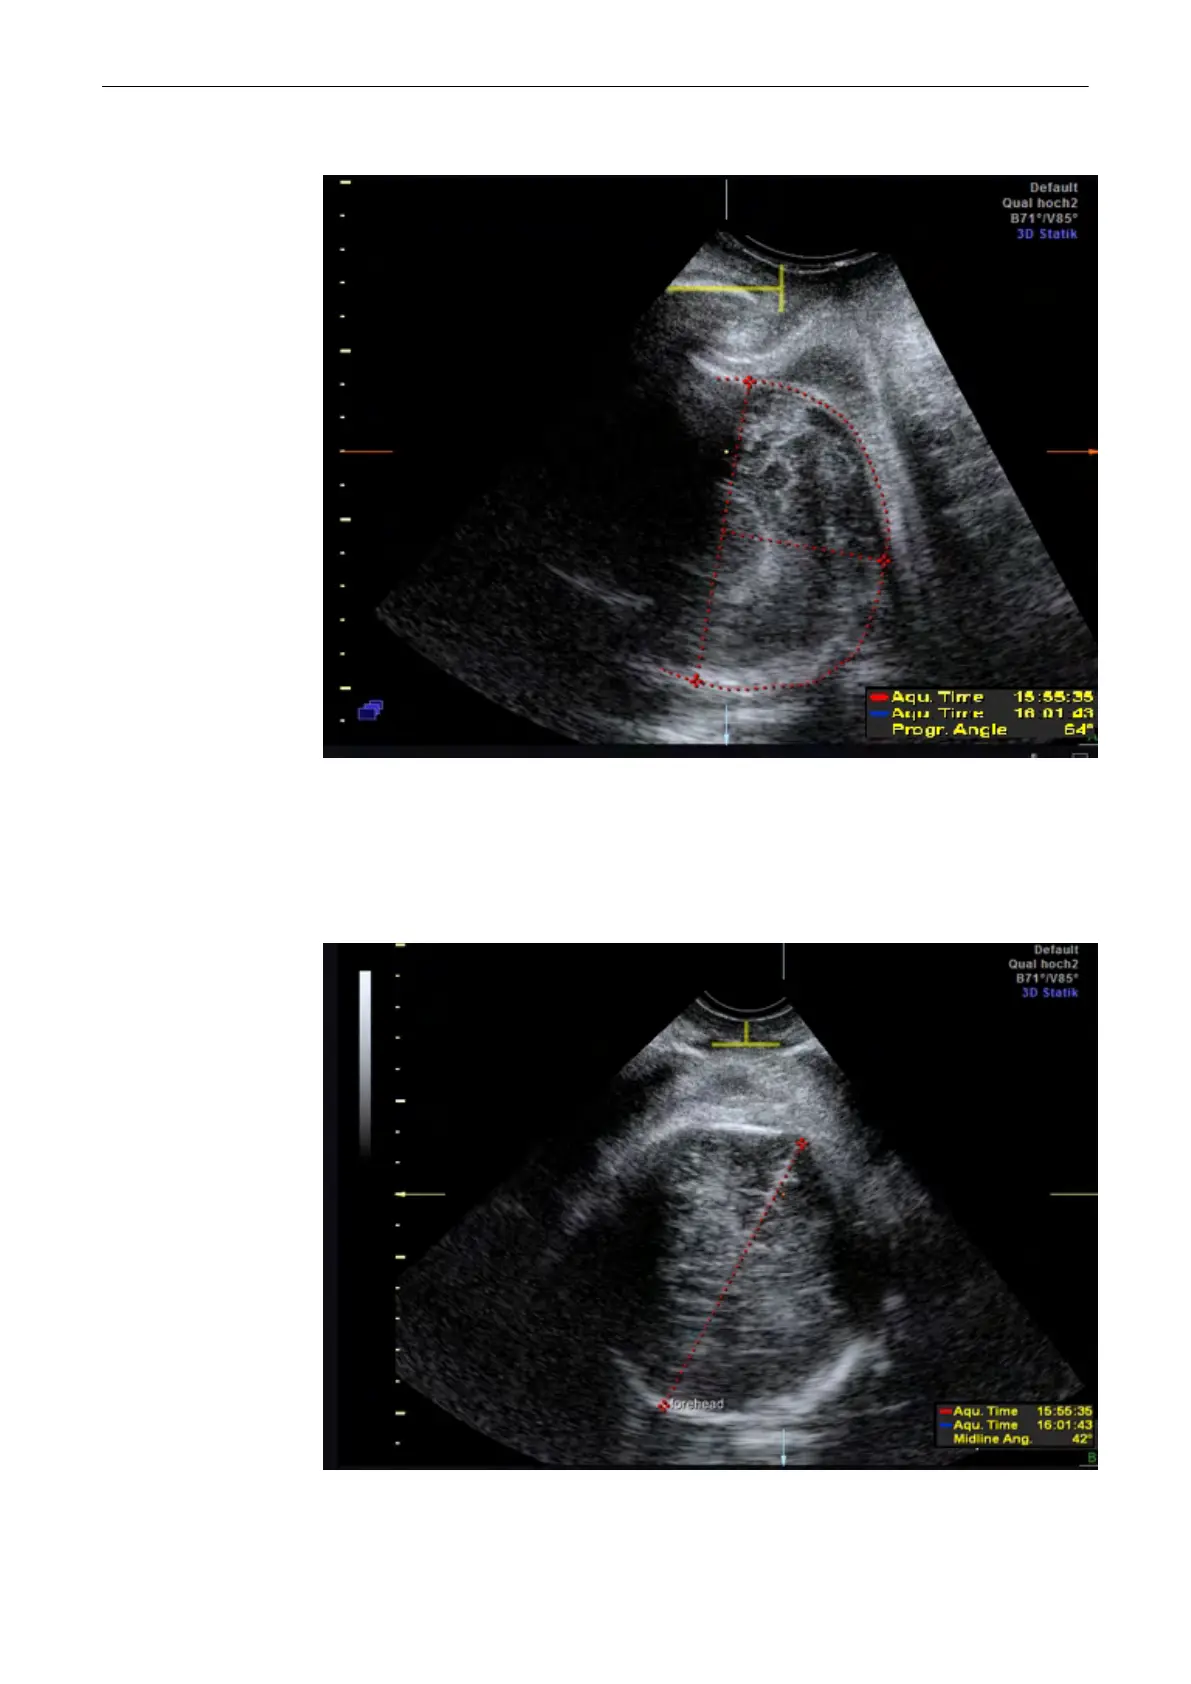

9.15.6 Set midline

Mark the position of the midline with a line of two points. The measurement result is the

calculated angle between the vertical axis and the midline. As the rotation can be to the left or

to the right it is necessary to start measuring at the occiput to get acurate results.